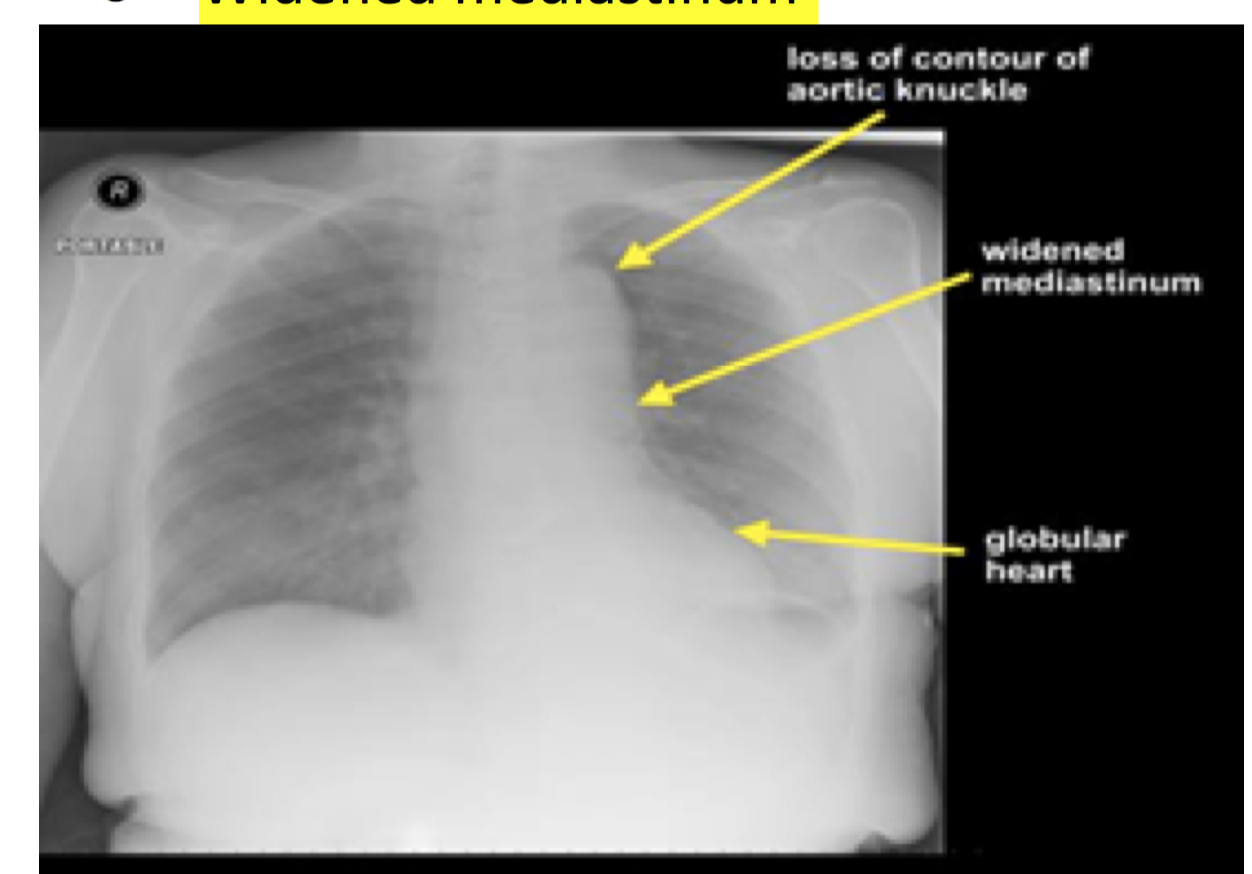

what can be seen on the CXR in aortic dissection?

( exclude other pulmonary causes of chest pain )

widened mediastinum